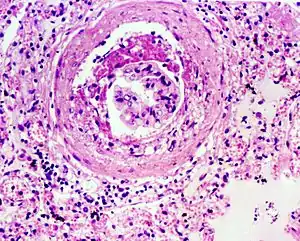

Glomerulosclerosis

Glomerulosclerosis is hardening of the glomeruli in the kidney. It is a general term to describe scarring of the kidneys' tiny blood vessels, the glomeruli, the functional units in the kidney that filter urea from the blood.

Proteinuria (large amounts of protein in urine) is one of the signs of glomerulosclerosis. Scarring disturbs the filtering process of the kidneys and allows protein to leak from the blood into urine. However, glomerulosclerosis is one of many causes of proteinuria. A kidney biopsy (removal of tiny part of kidney with a needle) may be necessary to determine whether a patient has glomerulosclerosis or another kidney problem. About 15 percent of people with proteinuria turn out to have glomerulosclerosis.